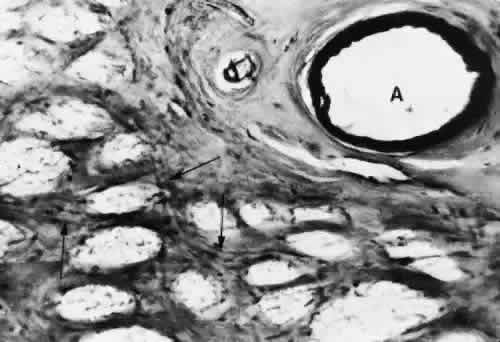

With aging, the connective tissue adjacent toand surrounding the choriocapillaris undergoeschanges, and electron-dense filaments and wide-spacing collagen may be seen. The main nerve supply to the choroid is from the ciliary nerves. A significant proportion of the fibers innervate the blood vessels and belong to the sympathetic nervous system. Delicate plexuses and ganglion cells are found in the surrounding connective tissue, and unmyelinated fibers course toward the vessel wall.62 CILIARY BODY AND IRIS The arterial blood supply to the ciliary body is from the branches of the long PCA, branches of the anterior ciliary arteries, and branches from the major arterial circle. Funk and Rohen,63 using scanning electron microscopy of resin casts of the ciliary body and iris vessels, have contributed significantly to our understanding of the anatomy of these vessels. They found that the perforating branches of the anterior ciliary arteries form an intramuscular circle that supplies the outer and posterior portions of the ciliary muscle, the iris, and the anterior choroid. The major circle of the iris is located more anteriorly and is supplied by the long PCAs and branches from the anterior ciliary arteries. The iridic major circle contributes to the anterior supply of the ciliary body as well as to the iris and ciliary processes. The ciliary processes themselves have three distinct vascular territories, each with its own system of arterioles and venules.63 The small arteries of the stroma of the ciliary body contain an endothelium and basement membrane, a poorly developed elastic lamina, a media containing two or three layers of smooth muscle, and a loose collagenous adventitia. Most ciliary vessels drain posteriorly into the choroidal and vortex systems. The remaining drainage is into the intrascleral venous plexus and the episcleral veins of the limbal region. Small veins and venules are found in the ciliary processes along with the capillaries. These vessels are often closely apposed to the pigmented layer of the epithelium surrounding the ciliary processes. The capillaries and venules of the ciliary body are 15 to 30 μm in diameter and are fenestrated in both the pars plicata and pars plana. They closely resemble the capillaries of the choriocapillaris except that they are smaller. The fenestrae of these vessels range in size from 300 to 1,000 nm in diameter.64 The major difference between the capillaries in different areas of the ciliary body is that only those of the pars plana are in contact with the elastica of Bruch's membrane on the surface facing the pigmented epithelium. The capillaries present in the ciliary muscle are nonfenestrated (Figs. 16 and 17). The blood vessels are innervated by small branches of sympathetic fibers. The iris blood vessels derive from the major iridic arterial circle and drain into the vortex system. The blood vessels of the iris are believed to have a slight corkscrew shape so they can accommodate to the changes in the length of the iris during dilation and contraction. A striking finding in all the iris vessels is the presence of thick collagenous adventitia that is several microns thick. There are approximately 200 radial vessels in the iris. The density of these vessels is greater than expected for the nutrition of the iris, and they probably account for anterior-segment thermal homeostasis and provide a high oxygen content for the corneal endothelium. Most of the vessels in the iris stoma are arterioles (Figs. 18, 19, and 20), venules, and capillaries (Fig. 21). The capillaries have unfenestrated endothelium with tight junctions. The main branches of these radial vessels form an incomplete circular arterial ring at the collarette (minor iris circle). Branches from the minor circle extend into the pupillary region to form capillary arcades. The venous drainage system parallels the arterial inflow pattern. The radial arteries of the iris are truly arterioles, with an overall diameter of 15 to 50 μm. The radial iridial veins are technically pericytic venules. They are approximately 30 to 90 μm in diameter. The media consists of one or two layers of pericytes. These cells make frequent contact with the endothelial cells but not with each other.